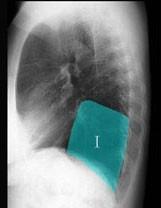

在图所示正常胸部X线影像图像上,该英文字母所代表的肺段为 ( )A、后基底段B、背段C、前基底段D、外基底段E、内基底段

问题 在图所示正常胸部X线影像图像上,该英文字母所代表的肺段为 ( )

选项 A、后基底段 B、背段 C、前基底段 D、外基底段 E、内基底段

答案 A